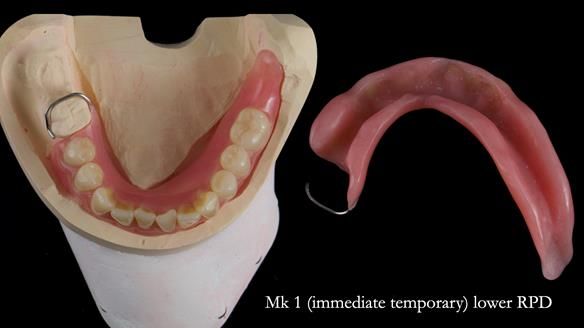

- Mk 1 lower immediate acrylic-based RPD

The original plan was to finish the lower as a conventional metal-based partial denture, as shown in the initial design below.